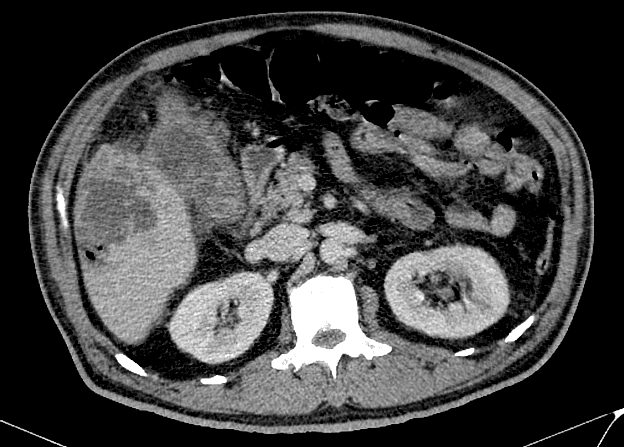

Viêm túi mật

» Thông tin: Nam giới – 60 tuổi.

» Lâm sàng: Đau bụng cấp.

# Viêm túi mật cấp biến chứng vỡ => Apxe gan.